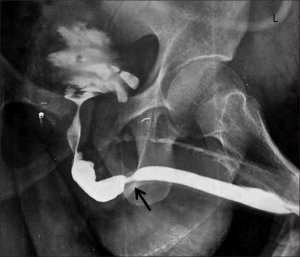

باریک شدن مجرای ادراری می تواند در کودکان، بزرگسالان ،مردان یا زنان اتفاق بیفتد. تنگی مجرای ادراری بیماری خطرناکی است